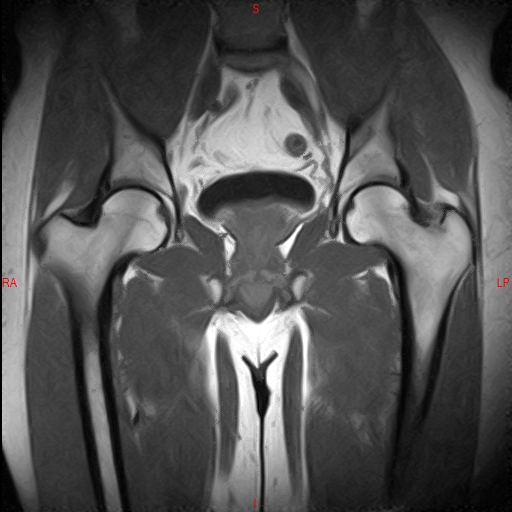

• Resonancia NORMAL CADERAS T2 CORONAL

• Resonancia NORMAL CADERAS T1 CORONAL